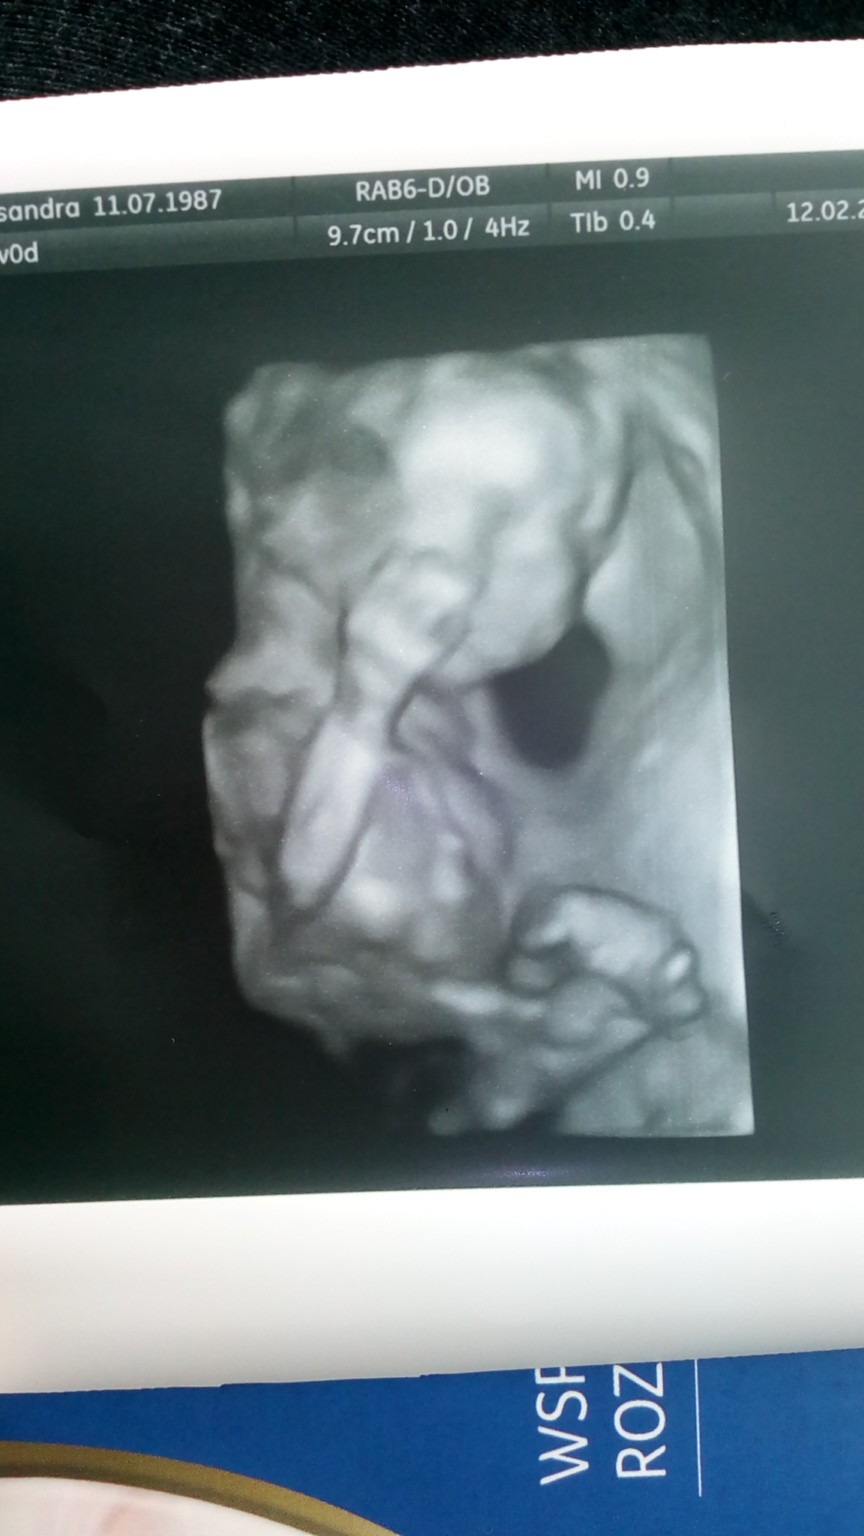

Już po wizycie :) Chłopiec! [emoji7] Wszystko ok. Mamy zapis na 4d. Mały cały czas machał rączkami i nóżkami. Wg USG 19+0 czyli idealnie jak z om. Waży 284 g. Ułożenie główkowe, łożysko na przedniej ścianie więc pewnie dlatego słabo czuje kopniaczki :)